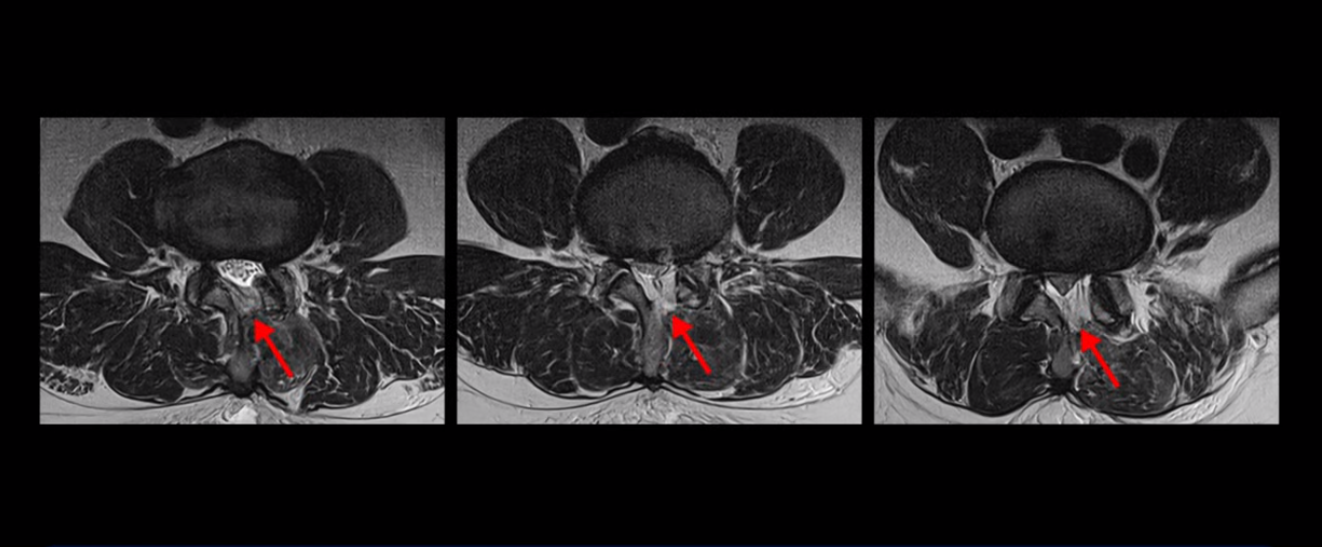

MRI 보면 무려 3마디의 허리 뒤쪽, 후궁 뼈 한쪽을 거의 다 뜯어내고

황색 인대를 대부분 다 걷어냈습니다.

문제는 이 허리 협착이 양손과 양쪽 다리 힘 빠짐의 원인이 아니었기에 수술 후에도 증상이 전혀 좋아지질 않습니다. 그나마 다행인 건 허리 여러 마디를 수술하면서도 나사를 안 박은 겁니다. 수술로 인해 허리 여러 마디에 손상이 생기니까 걷기가 더 어려워져서 결국 저희 병원에 오실 때는 휠체어를 타고 오셨습니다.